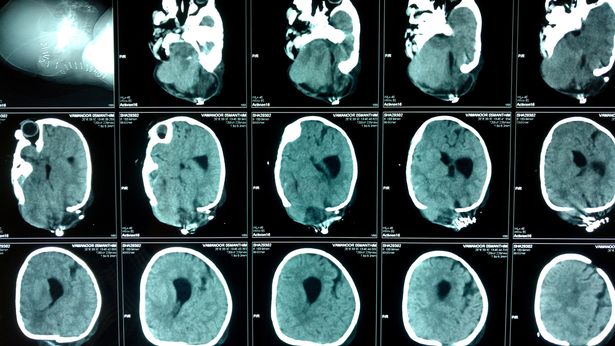

Il 27 marzo, il piccolo è stato sottoposto all’operazione per la rimozione della seconda “testa” e l’intervento è durato quasi 6 ore. Le speranze di successo erano minime perché i bambini piccoli non possono perdere troppo sangue. Un neurochirurgo che si è occupato del caso ha spiegato che il problema di Yamanoor è stato causato dalla mancanza di acido folico nel corpo della madre. Il piccolo è stato dimesso dall’ospedale e le sue condizioni sono buone, anche se ogni 3 mesi dovrà fare dei controlli.